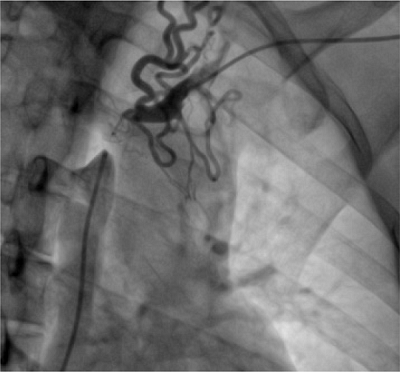

A 35-year-old male patient with a history of chronic autoimmune renal failure on hemodialysis for four years required placement of several jugular indwelling catheters and developed SVCS in the last two years. At an outside hospital, they failed doing endovascular therapy. The patient was transferred to our institution looking for definitive treatment. Computed tomography (CT) and invasive angiography imaging confirmed diagnosis (Figure 1). A new attempt of percutaneous management was done; nevertheless, complete occlusion of the brachiocephalic vein and SVC was found, then surgical treatment was decided.